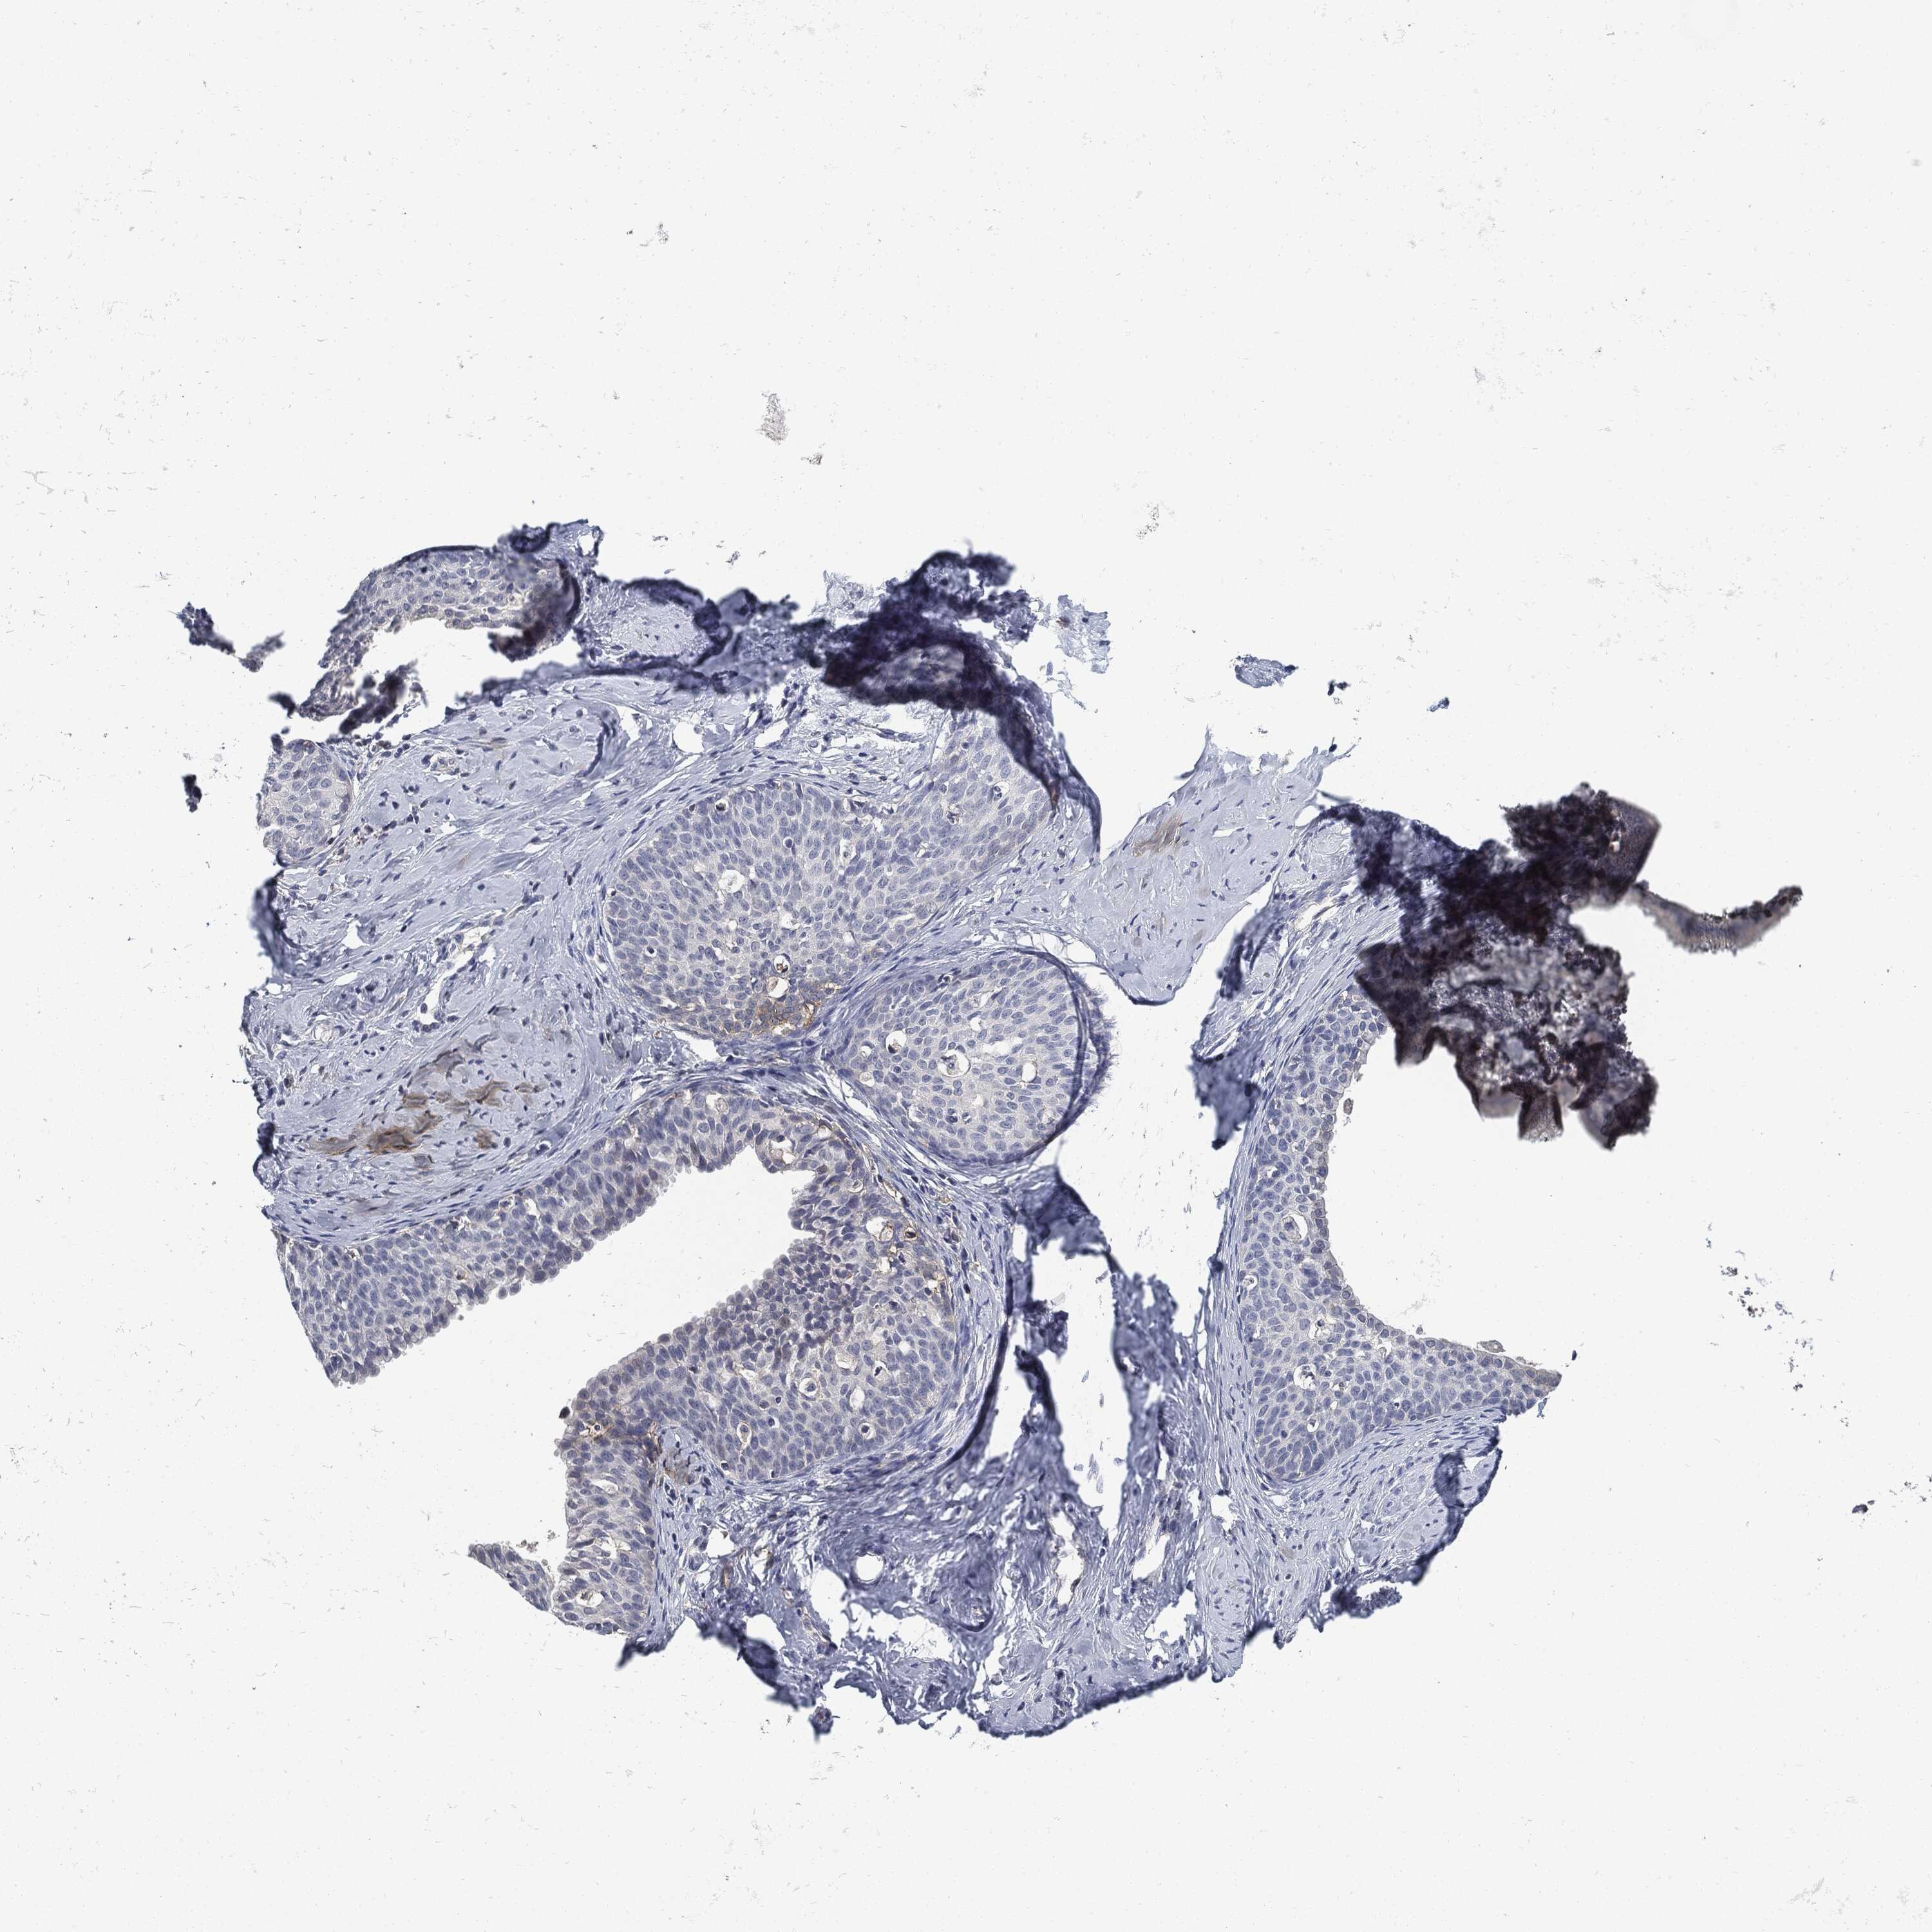

CERVICAL CANCER - Protein expressioni

A mouse-over function shows sample information and annotation data. Click on an image to view it in a full screen mode. Samples can be filtered based on level of antibody staining by selecting one or several of the following categories: high, medium, low and not detected. The assay and annotation is described here.

Note that samples used for immunohistochemistry by the Human Protein Atlas do not correspond to samples in the TCGA dataset.

Antibody stainingi

Antibody staining in the annotated cell types in the current human tissue is reported as not detected, low, medium, or high, based on conventional immunohistochemistry profiling in selected tissues. This score is based on the combination of the staining intensity and fraction of stained cells.

Each image is clickable and will lead to virtual microscopy that enables deeper exploration of all samples and also displays staining intensity scores, fraction scores and subcellular localization as well as patient and tissue information for each sample.

Antibody CAB076385

Antibody CAB080537

Staining

High

Medium

Low

Not detected

Intensity

Strong

Moderate

Weak

Negative

Quantity

>75%

75%-25%

<25%

None

Location

Nuclear

Cytoplasmic/membranous

Cytoplasmic/membranous,nuclear

Squamous cell carcinoma, NOS

Adenocarcinoma, NOS